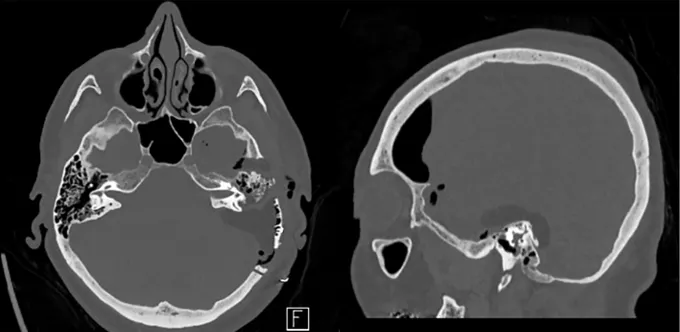

具体分析:MRI显示一个球形病变占据垂体漏斗后部及鞍上间隙,且肿瘤与垂体柄和正常垂体组织紧密相邻(黄色箭头)。

视交叉(绿色箭头)和动眼神经(蓝色箭头)由于受到肿瘤挤压而产生移位,视交叉已经变薄。此外,肿瘤与颈动脉(白色星号)、后交通动脉(红色箭头)、大脑前动脉(白色星号)和大脑后动脉(黄色箭头)紧密粘连,术中剥离困难,存在较大的出血风险。

要求:手术必须要在保留垂体及其功能的基础上进行安全切除,同时不损伤周围重要神经血管,谨慎将肿瘤与其剥离开来。

福教授策略:放弃经鼻内镜入路(EEA),选择经后岩骨入路。选择该入路是因为其脑脊液漏的风险有限,并且能够在颞叶下方提供从后到前、从下到上和从外侧到内侧的手术视野,旨在保留位于病变右侧的垂体柄。此外,手术以患者的预后为主要考量要素,而非追求全切。

具体分析:由于已知该肿瘤的血供丰富,福教授在手术前进行了DSA检查,显示其供血动脉主要为左侧垂体上的动脉(黄色箭头)。

福教授策略:进行术前栓塞确定供血动脉,且对颅底硬脑膜分支血管的近端闭塞对神经缺血的风险较小。栓塞后的血管造影显示肿瘤的供血动脉重建达到90%,线圈在垂体上动脉内可见(黄色箭头)。